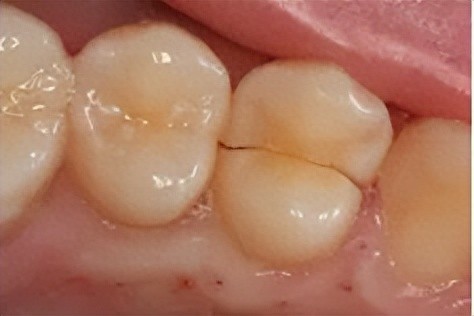

牙隐裂,又称不全牙裂或牙微裂,是指牙齿表面由于承受异常咬合力而产生的非生理性细小裂纹。这种裂纹在早期常不易被发现,但随着裂纹加深,可能会引起牙齿敏感、咀嚼不适、咬合痛或自发痛等症状。牙隐裂是牙齿敏感及牙痛的原因之一。

1. 先天发育不足:牙齿表面有发育沟,沟深的牙齿容易出现牙隐裂。

2. 牙齿过度“疲劳”:尤其是上颌第一磨牙,由于其解剖特点和使用频率,容易出现疲劳性隐裂。